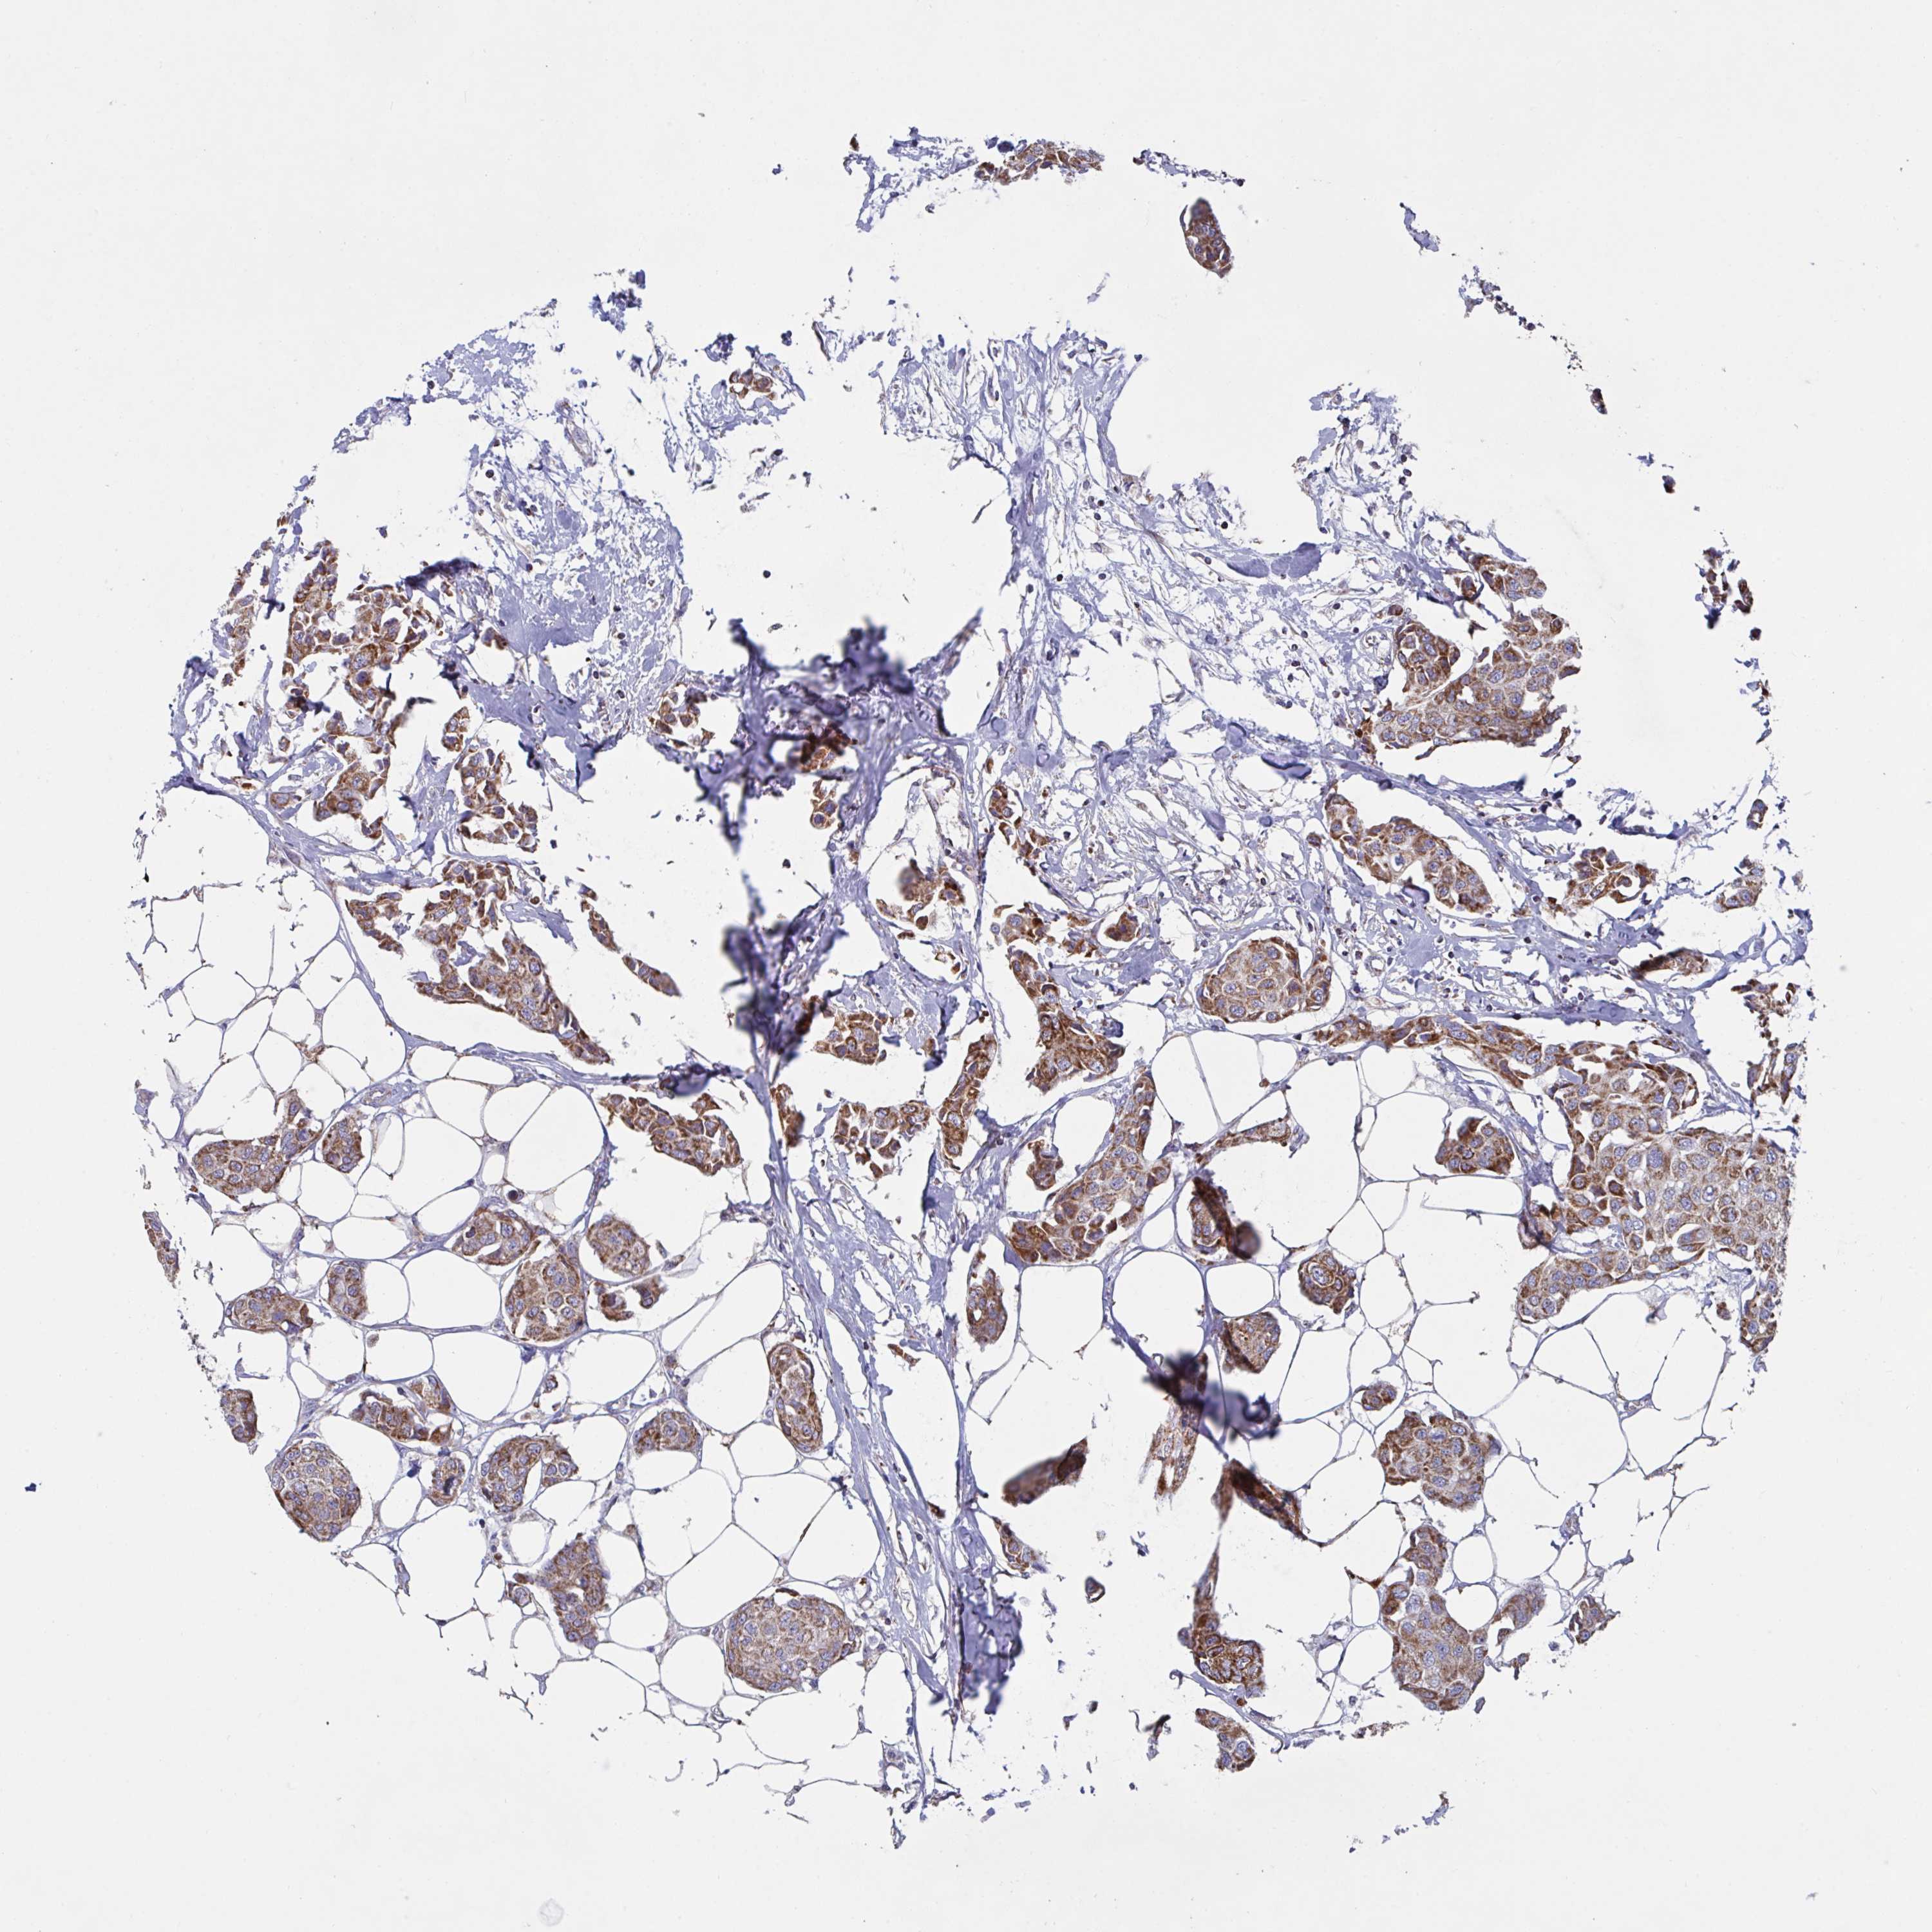

CANCER BREAST CANCER Show tissue menu

BRCA TCGA BRCA VALIDATION PROTEIN EXPRESSION